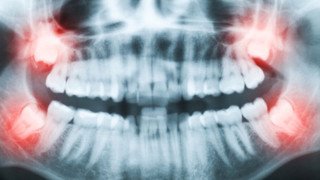

Tarkusehammaste eemaldamine

Tarkusehambad ehk kolmandad purihambad ei pruugi alati lõikuda õigesti või üldse lõikuda. Osaliselt lõikunud või täielikult igemesse või lõualuusse peetunud tarkusehambad tuleks sageli eemaldada ka siis, kui hetkel kaebusi ei esine.

Põhjuseks on mitmed võimalikud tüsistused:

- lõualuu tsüstide ja põletike teke,

- naaberhammastele kahjustamine või nende asendi muutumine,

- närvivalu,

- limaskestapõletik osaliselt lõikunud hamba ümbruses, mis võib muutuda ohtlikuks.

Selliste seisundite ennetamiseks on soovitatav peetunud või vales asendis tarkusehambad eemaldada enne sümptomite tekkimist.

Tarkusehamba eemaldamise keerukus sõltub selle asendist ja peetumuse astmest. Protseduur võib toimuda tavakliinikus kohaliku tuimestusega või vajadusel näo- ja lõualuukirurgi käe all.